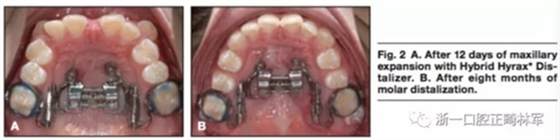

局麻下將兩枚2mm*9mm的微種植體植入鄰近腭中縫處。在上頜第一前磨牙處使用不銹鋼絲。使用聚乙烯硅氧烷上頜取模以制造Hybrid。局麻下翻開粘骨膜瓣使用4枚皮質(zhì)釘以在下頜前牙放置鈦板。通過轉(zhuǎn)動(dòng)矢狀向的螺釘90°4次以激活擴(kuò)弓器,0.2mm每次,0.8mm每天。鈦板使用皮筋在兩側(cè)直接加400g前牽力。12天后,上頜前磨牙間橫向?qū)挾仍黾拥?mm。(圖2,A)矢狀螺釘在磨牙遠(yuǎn)移階段固定,每周激活雙側(cè)遠(yuǎn)移螺釘(0.2mm每周)。8個(gè)月后磨牙遠(yuǎn)移4mm(圖2B),該階段繼續(xù)掛皮筋。